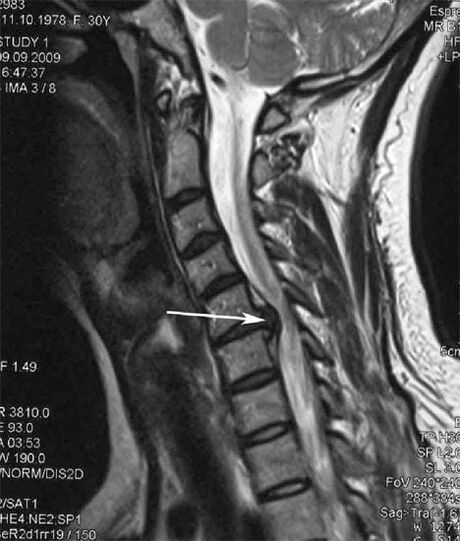

V začetnih fazah se osteohondroza odkrije z MRI. Kasneje lahko patologijo diagnosticiramo z radiografijo. Na radiografiji vratne hrbtenice je opazno zmanjšanje razdalje med vretenci, patološke spremembe v fasetnih sklepih in osteofitoza.

Mnogi ljudje se pritožujejo, da ne morejo obrniti vratu zaradi hude bolečine, ki se pojavi po nenadnem dvigovanju težkega. Ta pojav kaže na nastanek hernije diska. Vzrok bolečine v hrbtu, vratu in zgornjih okončinah je ukleščenje ene od živčnih korenin, ki izhajajo iz hrbtenjače.

| Cervikalna osteohondroza | Pojav patoloških sprememb v enem ali več segmentih gibanja hrbtenice. Motena gibljivost hrbtenice, razvoj miofascialnih bolečinskih sindromov in stiskanje hrbteničnih korenin. | Bolečina, parestezija in motorične motnje v predelu materničnega vratu, ki se razširijo na zadnji del glave in zgornje okončine. Odkrivanje značilnih sprememb hrbtenice na MRI in rentgenskih slikah (osteofiti, zmanjšana razdalja med vretenci, znaki poškodb medvretenčnih sklepov) |